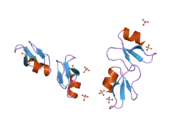

Beta-defensin 1 is a protein that in humans is encoded by the DEFB1 gene.[3][4]

Defensins form a family of microbicidal and cytotoxic peptides made by neutrophils. Members of the defensin family are highly similar in protein sequence. This gene encodes defensin, beta 1, an antimicrobial peptide implicated in the resistance of epithelial surfaces to microbial colonization. This gene maps in close proximity to defensin family member defensin, alpha 1, and has been implicated in the pathogenesis of cystic fibrosis.[4] Single-nucleotide polymorphisms in the DEFB1 gene were associated with plasma kynurenine concentrations in major depressive disorder patients in a genome-wide association study.[5]

- Hoover DM, Chertov O, Lubkowski J (October 2001). "The structure of human beta-defensin-1: new insights into structural properties of beta-defensins". The Journal of Biological Chemistry. 276 (42): 39021–6. doi:10.1074/jbc.M103830200. PMID 11486002.